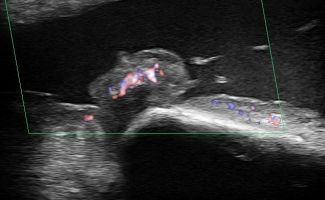

- Fluid collection in the bursa (i.e olecranon bursitis)

- Synovitis in the bursa as a symptom of Rheumatologic Disease